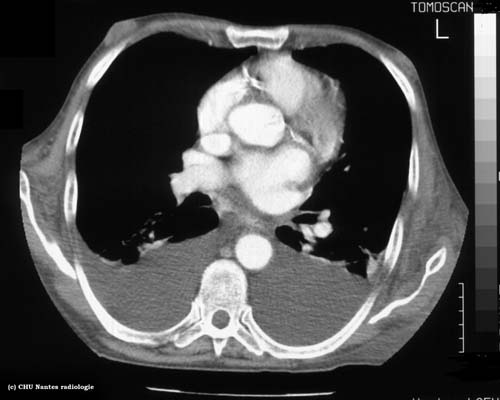

Epanchements liquidiens :coupe

TDM